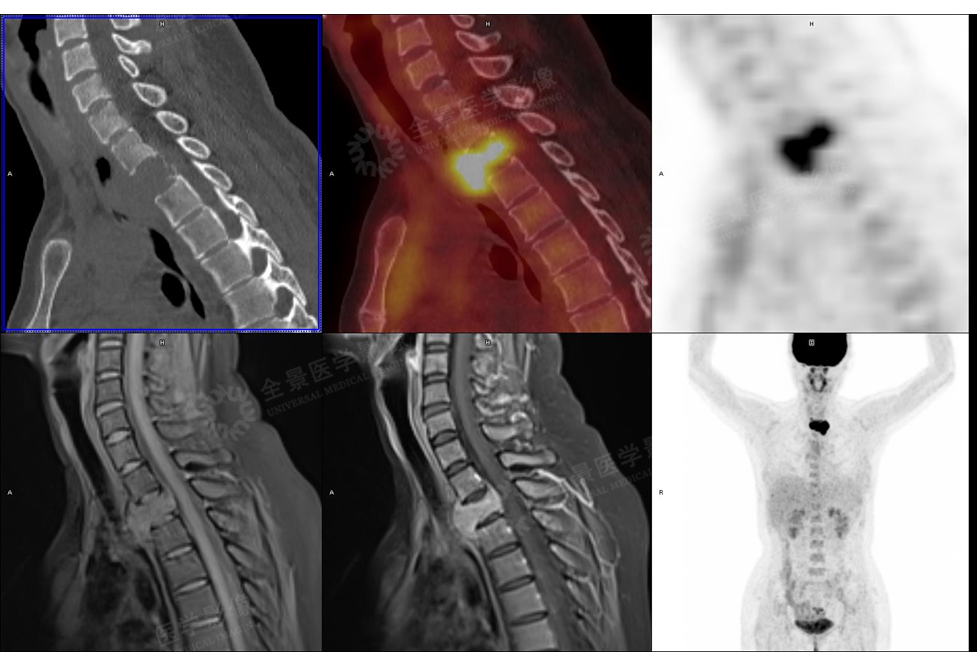

骨关节

案例 :骨巨细胞瘤

T2WI不均匀等信号,

PET/CT显示:T3骨质破坏并周围软组织肿块形成,FDG明显摄取增高。

增强扫描明显强化